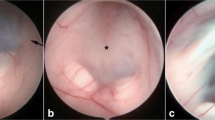

Endoscopic third ventriculostomy (ETV) is a minimally invasive procedure of cerebrospinal fluid (CSF) diversion widely used for treating hydrocephalus of various etiologies [1–3] with a success rate of 68.5–83% [1, 4–6]. This technique involves passing a rigid endoscope through the CSF spaces of the ventricular system to access and fenestrate the floor of the third ventricle. The linear working trajectory for this procedure passes adjacent to multiple eloquent periventricular structures such as the fornix, caudate nucleus, genu of the internal capsule, and hypothalamus (Fig. 1). Excessive manipulation to these structures can cause disturbance in motor, memory, speech, and endocrine functions leading to a permanent morbidity or mortality [7]. Furthermore, injury to adjacent vascular structures such as the choroid plexus, thalamostriate vein, or potentially major arteries can lead to devastating bleeding. Previous studies recommended optimal ETV entry points that provide an atraumatic trajectory avoiding these structures [8–10]. The location of these points however varies considerably which is paralleled by the highly diverse morphology of the ventricles in hydrocephalus [9, 11, 12]. These observations suggest that ETV entry points should be planned on a case-by-case basis with adjustments based on the ventricle sizes [13, 14]. Neuronavigation is now well-accepted in neurosurgical practice, however, it has not been widely used for ETV planning as most studies report using a single conventional transcortical entry point [1, 4–6, 14]. Furthermore, the infrastructure to this adjunct is not always available to the surgeon. We therefore examined the correlation between ventricular morphometry and the location of the optimal ETV entry points in 30 pediatric patients with a specific view to creating a surgical planning aid.

Surgical anatomy of the third ventriculostomy and the concept of optimal ETV trajectory. A: schematic showing optimal ETV trajectory (interrupted line) aligned along the foramen of Monro and the third ventricle floor. B and C: diagram depicting the operative view and eloquent periventricular structures at the level of the foramen of Monro (B) and the third ventricle floor (C). Panel B: eloquent structures are highlighted as follows, brown: fornix; yellow: caudate nucleus; green: genu of internal capsule; red: thalamus. Panel C: yellow: chiasm; red: basilar artery termination; green: hypothalamus. Interrupted circle: fenestration site